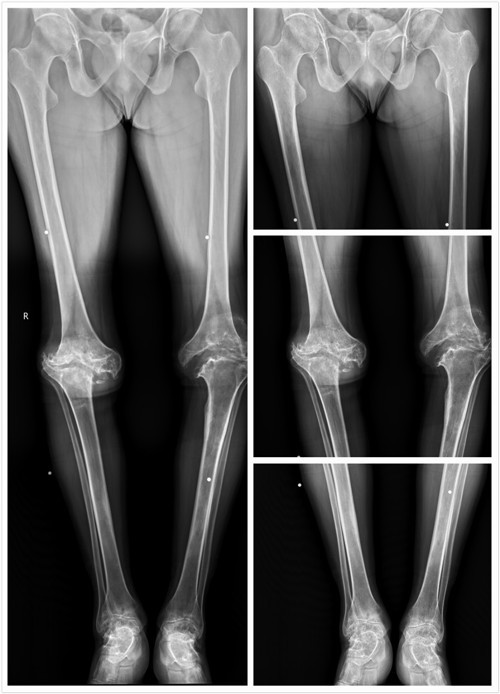

在一张照片上能观察到全脊柱一直是放射科医师及临床医师所希望的。全脊柱X线片对于脊柱侧弯的诊断、手术方案的制定、Cobb角度的测量等,都有着重要的参考价值。日前,交大二附院医学影像科购入的西班牙赛德科NOVA FA-C全自动悬吊摄影系统(DR拍片机),已顺利装机、调试和培训,该机器可一键定位(发射器与接收器一键跟随)、双板拍片(立位片与卧位片可在一个检查室进行)、自带床旁(直接在仪器旁对无法挪床的患者进行床旁射片)、图像拼接(将多张射片图像重叠合并生成全景或高分辨率图像)等新技术。

3月8日,在骨科与康复医学科的支持下,科室所有工作人员进行了图像拼接技术的培训及学习,顺利完成三例全脊柱和一例下肢全长的拼接摄影,取得了满意的效果。